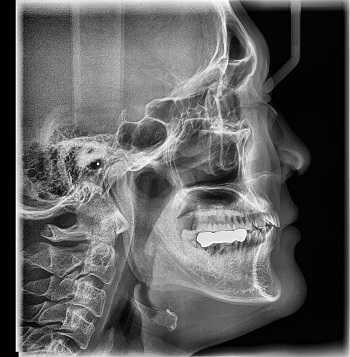

Рентген

Наиболее старый и привычный метод визуализации человеческого тела. Применяют рентген повсеместно, от хирургии до стоматологии. Метод прост и понятен: человека облучают особыми лучами, которые легко проходят сквозь мягкие ткани и задерживаются в твёрдых. Благодаря этому принципу, на фотоплёнку или датчик, расположенные на противоположной от источника лучей стороне, передаётся изображение, а в распоряжение врача попадает рентгенография или рентгеноскопия.

Главные плюсы такого обследования: быстрота и стоимость. Рентгеновскими аппаратами оснащены практически все больницы, процедура проходит быстро и стоит недорого.

Главные минусы: облучение и качество изображения. При проведении рентгенографии пациент облучается, а картинка получается двумерной. Врач с трудом может разглядеть внутренние органы по отдельности, поскольку их тени перекрывают друг друга. Также невозможно детально разглядеть хрящевую ткань и мозг. Хрящи практически не задерживает лучи, мозг надёжно закрыт черепной коробкой. Для их исследования рентгенография не подойдёт.

Наиболее эффективно будет проводить рентгенографию при повреждениях костей, суставов и зубов.

Что покажет рентген

Рентген - это самый широко доступный тип обследования. В Санкт-Петербурге его можно сделать быстро на платной или бесплатной основе как в частных, так и в государственных клиниках и больницах. Основная задача рентгенографии - дать общее представление об изменении структуры органов и костной ткани. С помощью рентген-аппарата врач может хорошо визуализировать:

- инородные тела;

- переломы;

- воспаление легких;

- рак молочной железы;

- туберкулез.

Основное преимущество рентгенографии заключается в том, что это быстрый и дешевый метод сканирования. Однако по точности и диагностической ценности он безусловно уступает как УЗИ, так и таким высокотехнологичным методам исследования, как МРТ и КТ.

В основе физики работы рентген-аппарата лежат просвечивающие способности рентгеновских лучей. Получение плоского двухмерного изображения основано на ослаблении рентгеновского излучения при его прохождении через различные ткани. При рентген-сканировании пучок излучения, проходя через ткани организма, которые обладают различной плотностью, рассеивается и тормозится. Таким образом, на пленке возникают изображения разной степени интенсивности. Лучевая нагрузка при рентгенографии небольшая, но она всегда есть и может составлять от 0,1 до 1 мЗв. Поэтому рентгенография запрещена для беременных женщин, а здоровому человеку рентген можно делать 1- 2 раза в год.

Кроме дозы облучения у рентгеновского сканирования есть один существенный диагностический недостаток - плоская картинка. Поскольку рентген изображения - это тень ткани на пленке, объемно оценить органы и структуры человеческого тела с помощью рентгена не получается.

Рентгенография

Принцип работы рентгеновского аппарата заключается в том, что рентгеновские лучи, проходя через разноплотную среду исследуемой области, по-разному ослабляются: более плотная костная ткань в значительной степени поглощает рентгеновское излучение, менее плотная подкожно-жировая клетчатка ослабляет его в небольшой степени, а воздух, содержащийся в околоносовых пазухах или легких, не задерживает совсем. Эти неравномерно ослабленные пучки рентгеновских лучей, попадая на светочувствительный слой пленки, формируют рентгенограмму — изображение, которое отображает все структуры исследуемой области, наслаивая их друг на друга. При этом получаемый снимок позволяет определить форму, размеры и строение исследуемой области, выявить или заподозрить структурные нарушения, а исследование в двух или нескольких проекциях позволяет определить локализацию выявленных изменений. Чаще всего рентгенография используется для исследования костей, легких, почек, кишечника.

C самого начала существования этот метод диагностики вызывал у пациентов множество вопросов по поводу воздействия рентгеновского излучения на организм. На сегодняшний день специалисты подтвердили вред рентгена и его способность влиять на развитие нежелательных процессов в организме. Тем не менее, этот метод лучевой диагностики продолжает пользоваться спросом, поскольку требует минимальных затрат.